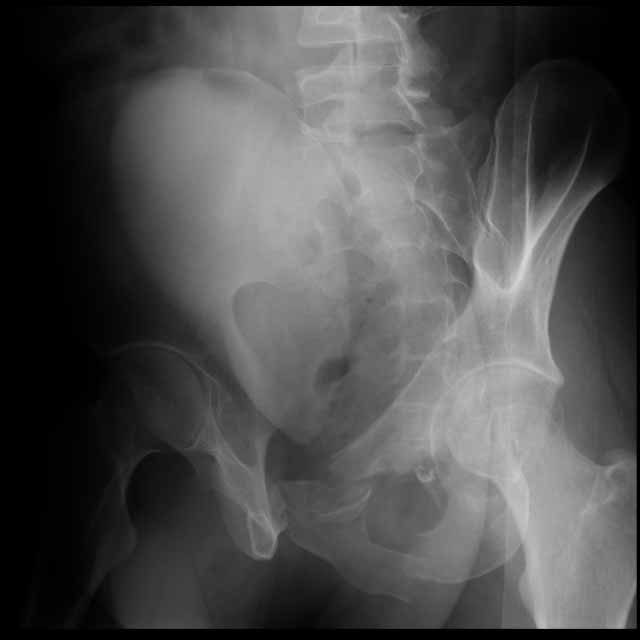

25 yo brittle diabetic, became hypoglycemic and passed out on his motorcycle. Sustained bilateral lateral Hoffa fractures with associated LCL injury on the right and right distal radius fracture. I have questions regarding his pelvic ring/acetabular fracture on the left. Appears to be a very low posterior column fracture with associated posterior wall, marginal impaction. Superior and inferior rami fractures as well on the left giving him a floating segment of inf ramus/ischium/posterior column, but no detectable posterior ring injury. Should the posterior column/posterior wall fracture be addressed surgically because of the marginal impaction? Or is this fracture low enough to be treated non-operatively? I appreciate the input.

I believe the more serious component of the acetabular fracture to be the large (almost 50%) impacted, comminuted zone of the posterior wall. In several series, including the one I reported at the AAOS in 2002 in Dallas of 100 acetabular fractures with posterior wall involvement, all repaired by a single surgeon (Kyle Dickson), those with posterior wall impaction did significantly worse than those without. Nevertheless, the large area of involvement, as well as a joint designed for very low tolerances of "out of round", would indicate that the best chance for avoiding early degenerative changes would be an anatomic repair.

It's an interesting case. The plain films show the impaction, but most of the joint looks pretty good. The CT cuts look awful, though.

The impaction is so big I don't think I would ignore it. It IS down low, but it takes up almost the whole southern hemisphere of his joint.